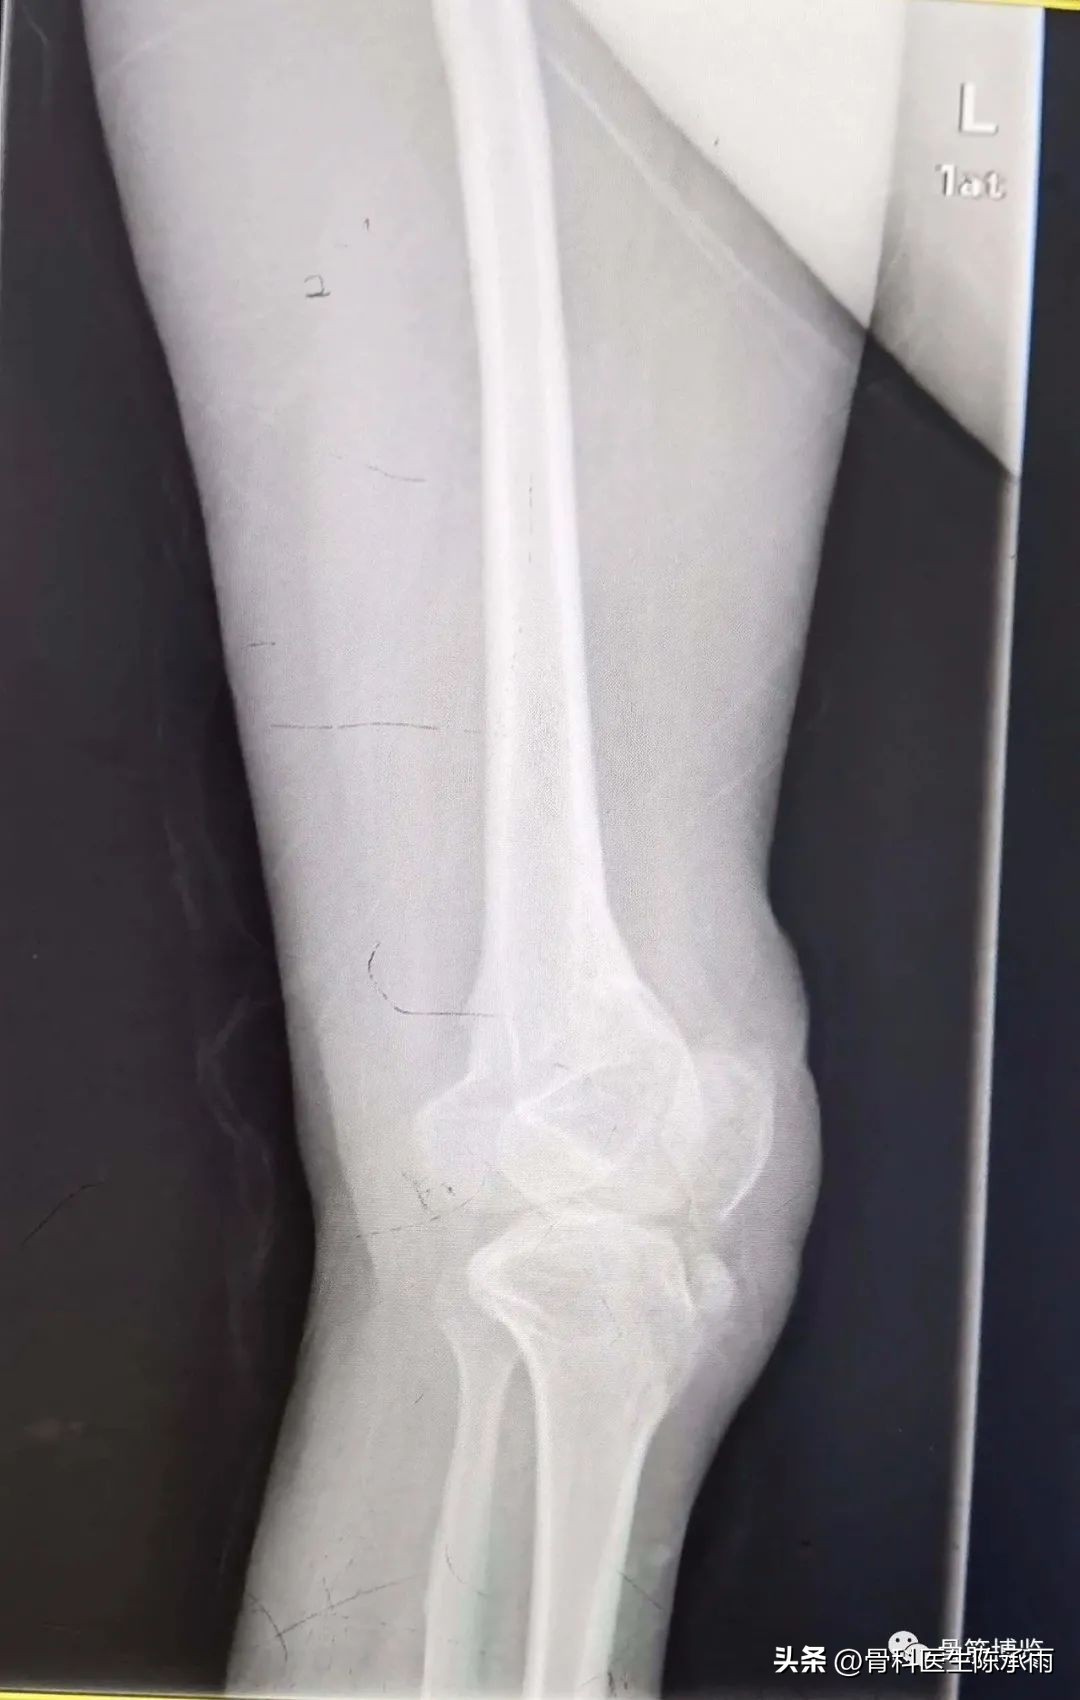

术后拍片由于患肢内旋畸形,未显示标准正位

6个月后复查

患者行走如受伤前,无疼痛,无明显不适